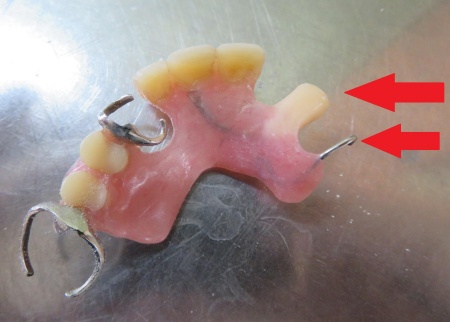

ご相談内容 「歯が折れて、入れ歯がうまく使えなくなってしまった」とご相談いただきました。

カウンセリング・診断結果 拝見したところ、左上の歯が折れて歯根だけが残っている状態でした。

これが原因で、入れ歯を固定する金属のバネ「クラスプ」をかける歯の土台が失われ、入れ歯が安定しなくなっています。

行ったご提案・治療内容 患者さんは1年前にクラスプの修理をされており、歯が折れるまでは問題なく使用していました。

1年前にクラスプの修理をした際の画像です。